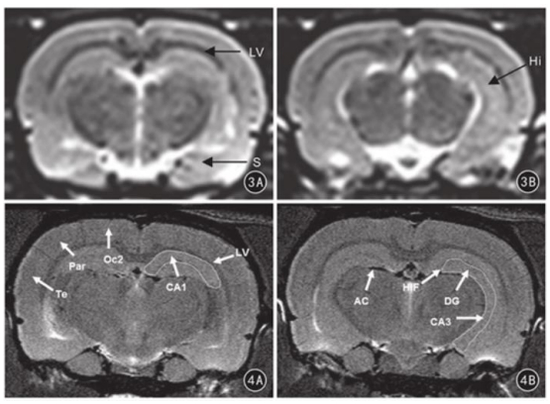

图表:7.0T核磁(下方)与3.0T核磁(上方)图像对比,清晰度显著提升

资料来源:李月峰等《基于灰度差分法的7.0 T及3.0   T MRI测量正常大鼠海马容积的对比研究》(2017年),中金公司研究部